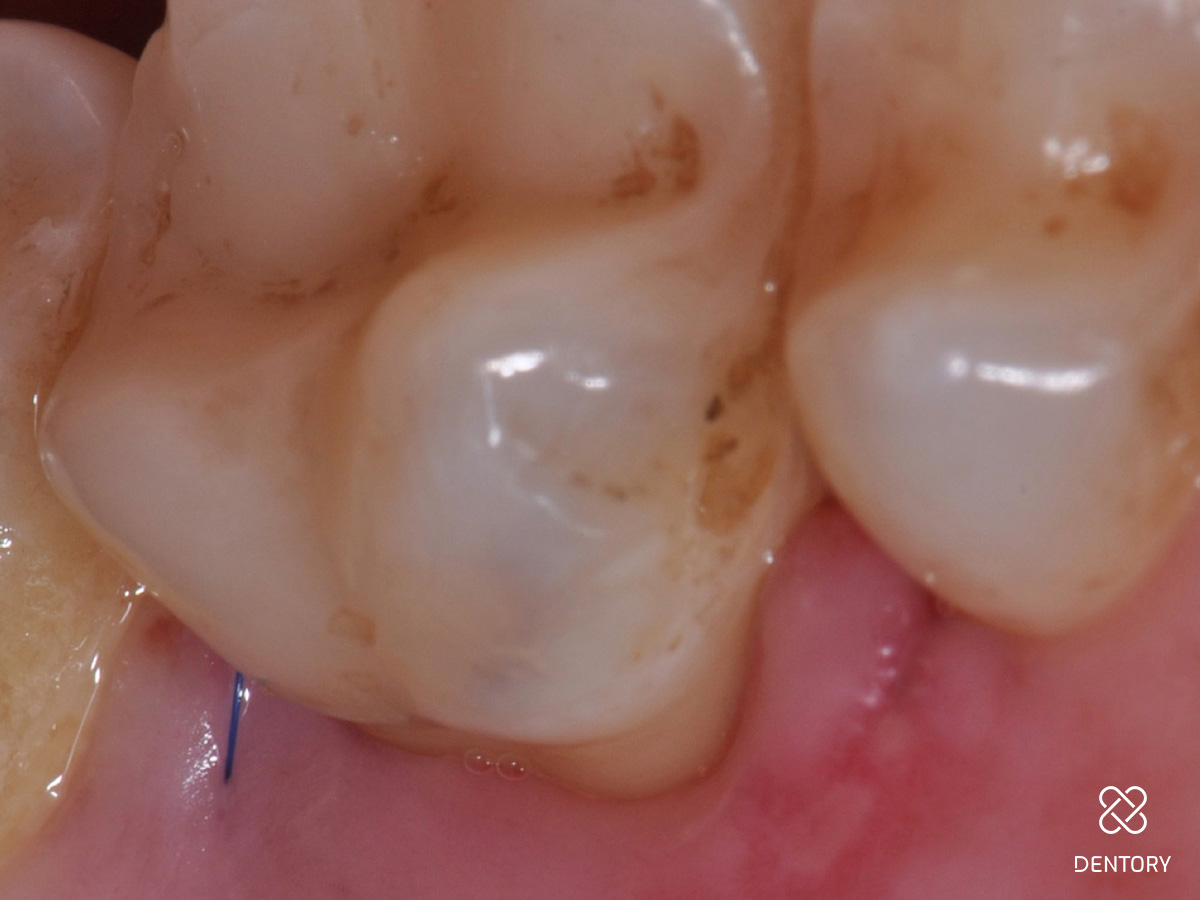

Abbildung 2

Die Ausgangssituation der regio 16/17. Hier wurden initial Sondierungstiefen von 9 und 11 mm mesial an Zahn 17 gemessen.